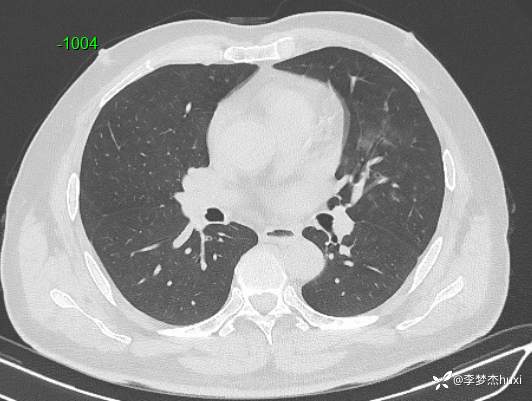

男性48岁,咯血3小时,咯血病因?

主诉:咯血3小时

简要病史:患者于入院前3小时无明显诱因出现咯血,为鲜红色,量较多,约10ml,伴胸闷、压气,伴咳嗽,无明显咳痰。

体格检查:T36.2℃,P110次/分,R20次/分,BP250/130mmHg。神清,呼吸平稳,浅表淋巴结不大,双肺叩清音,双肺未闻及干湿性啰音,心率110次/分,律齐,无杂音。腹部平坦,软,全腹无压痛,无反跳痛及肌紧张,肝脾肋下未触及,双下肢无水肿。

辅助检查:胸部CT:双肺炎症,双肺纹理增多,主动脉及冠状动脉钙化,主肺动脉稍增粗,右侧肾上腺点状高密度影,考虑脂肪肝。

临床诊断:肺炎咯血